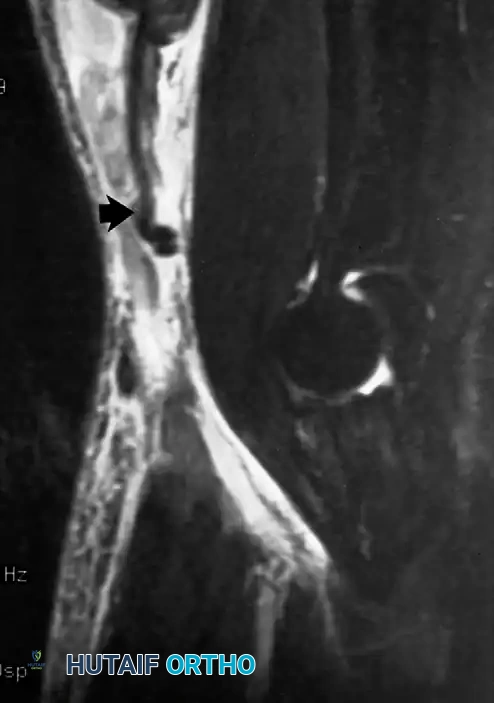

11. Pathology (11): The arrow points to an abnormality in the region of the coronoid fossa. This was associated with severe restriction of elbow flexion.

Diagnosis: this is a large loose body. In the single view the source is not obvious, but the most likely causes are osteochondritis

dissecans or osteoarthritis. The loss of flexion is due to a purely mechanical block to movement.